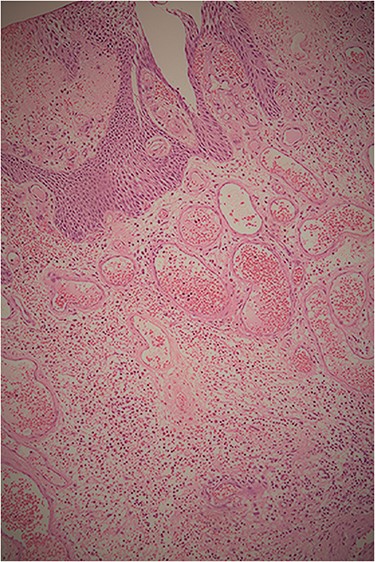

Histologically, the tumor had a polypoid structure supported by a large dense hypervascularized fibroconjunctive axis, with normal urothelium and without evidence of malignancy. This finding confirmed the diagnosis of a FP (Fig. 2).

Histopathological examination showing the tumor’s polypoid structure supported by a large dense hypervascularized fibroconjunctive axis, with normal urothelium and without evidence of malignancy.